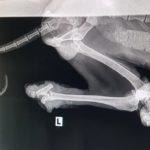

Жестоко насилие над куче край Кърджали. Животното е с отрязани задни крайници и без едно око. То е било намерено до язовир „Студен кладенец“. За щастие на помощ са му се притекли от фондация „Animal Hope Bulgaria“.

От фондацията са го кръстили Лъки-Иван. В социалната мрежа „Facebook“ те публикуваха снимки на кучето и информираха, че вече са храни отлично и излиза на разходка. Добри хора са отворили сърцата си и са дарили за раненото животно сумата от 1120,72 лева. За момента от фондацията спират събирането на средства. Те са необходими са операциите на краката на Лъки-Иван, които трябва да бъдат назначени днес, както и за закупуването на протези.